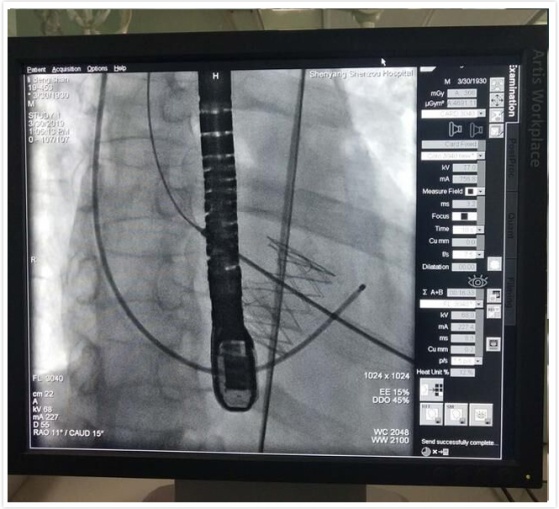

DSA下人工心脏瓣膜释放与固定

手术当日一早,手术相关科室通力协作,麻醉科、介入导管室进行了充分的麻醉及器械准备。11点手术正式开始, 全麻后,经左侧第五肋间小切口5cm依次经胸,显露心尖,双荷包缝合,穿刺心尖并置管,主动脉根部造影,显示:主动脉瓣重度关闭不全,根据术前CT和超声心动图测量的主动脉瓣环直径,选用29mm的J-Valve介入人工心脏瓣膜,植入原主动脉瓣环处。

再次造影及TEE显示:主动脉瓣无返流,介入瓣膜形态满意,无瓣周漏,无跨瓣压差。